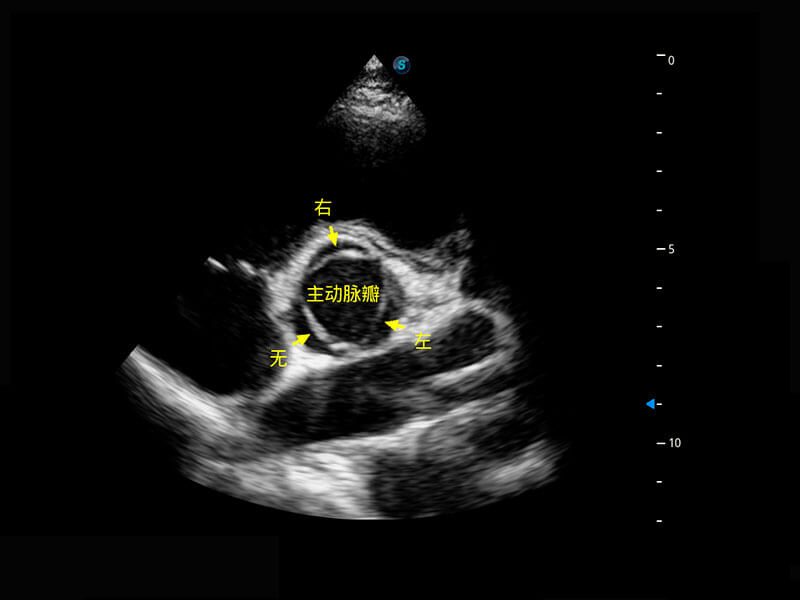

乳腺超声 / 新生儿

• 新生儿心脏